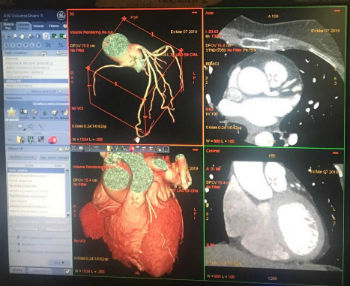

Enna. Attivato il servizio di Cardio Tac. Ne dà notizia il dr. Lello Vasco, direttore della U.O.C di Cardiologia. “La nostra Azienda da qualche anno persegue con determinazione il potenziamento della diagnostica cardiologica per immagini, per fare del Presidio Ospedaliero Umberto I di Enna un punto di riferimento per l’intero bacino. In atto, si è in condizione di garantire procedure complesse di diagnostica cardiologica che vanno dalla semplice ecocardiografia di base, passando per gli ecostress, per la scintigrafia miocardica fino ad arrivare alla cardio RM. Da oggi il cardiopatico potrà usufruire di un altro importantissimo servizio : La Cardio Tac per lo studio dell’anatomia coronarica. Il raggiungimento di tale importantissimo obiettivo è stato reso possibile da un gioco di squadra che ha visto protagonisti, non solo i medici, cardiologi e radiologi, ma anche gli uffici delegati al perfezionamento delle procedure di acquisto delle apparecchiature .

La Tac coronarica, studio non invasivo dell’anatomia dei vasi cardiaci permette di effettuare diagnosi sempre più selezionate, per esempio evidenziando preventivamente i pazienti da sottoporre ad angioplastica, by pass aorto coronarico o a semplice follow up clinico.

I pazienti così individuati dal cardiologo verranno sottoposti all’esame che sarà eseguito da un tecnico di radiologia in presenza del radiologo . Durante la procedura, il cardiologo interverrà per assicurare il mantenimento di condizioni emodinamiche stabili, riducendo la frequenza cardiaca e così permettendo l’acquisizione di immagini di alta qualità. In prima fila a occuparsi della metodica, sono il dr. Di Natale Roberto, radiologo, e le cardiologhe dr.sse Licata Pamela e Grasso Stefania.